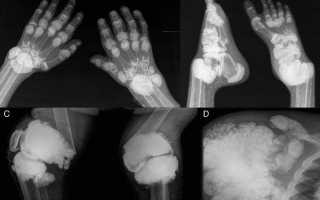

Подагра — ревматическое заболевание, причиной которого становятся тофусы, или кристаллы мочевой кислоты, постепенно накапливающиеся в полости сустава. Клинически патология проявляется рецидивами артрита. Человек страдает от мучительных болей в суставах, их отечности и скованности движений. Постепенно в патологический процесс вовлекаются почки — развивается мочекаменная болезнь. При тяжелом течении подагры у больных диагностируется почечная недостаточность. Нарушается мочевыделение, усиливаются отеки из-за задержки жидкости в организме.